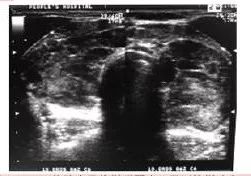

甲状腺彩超提示回声减低、增粗,不均匀,典型的呈网格状。